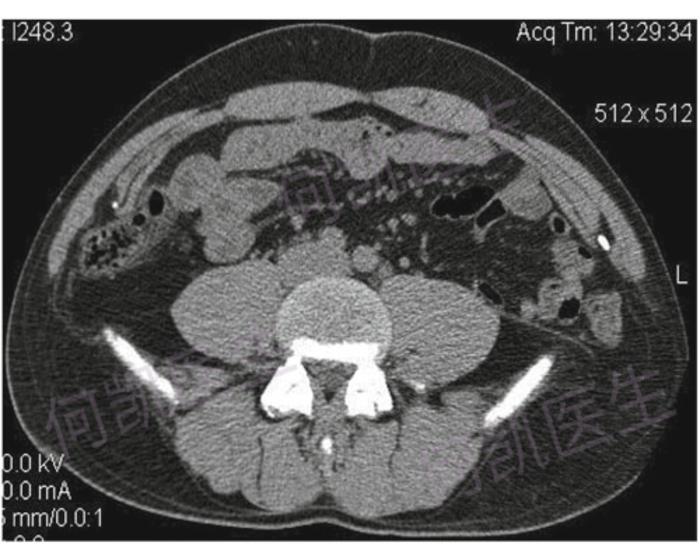

7种类型腹内疝的影像学表现

挺经典的腰疝